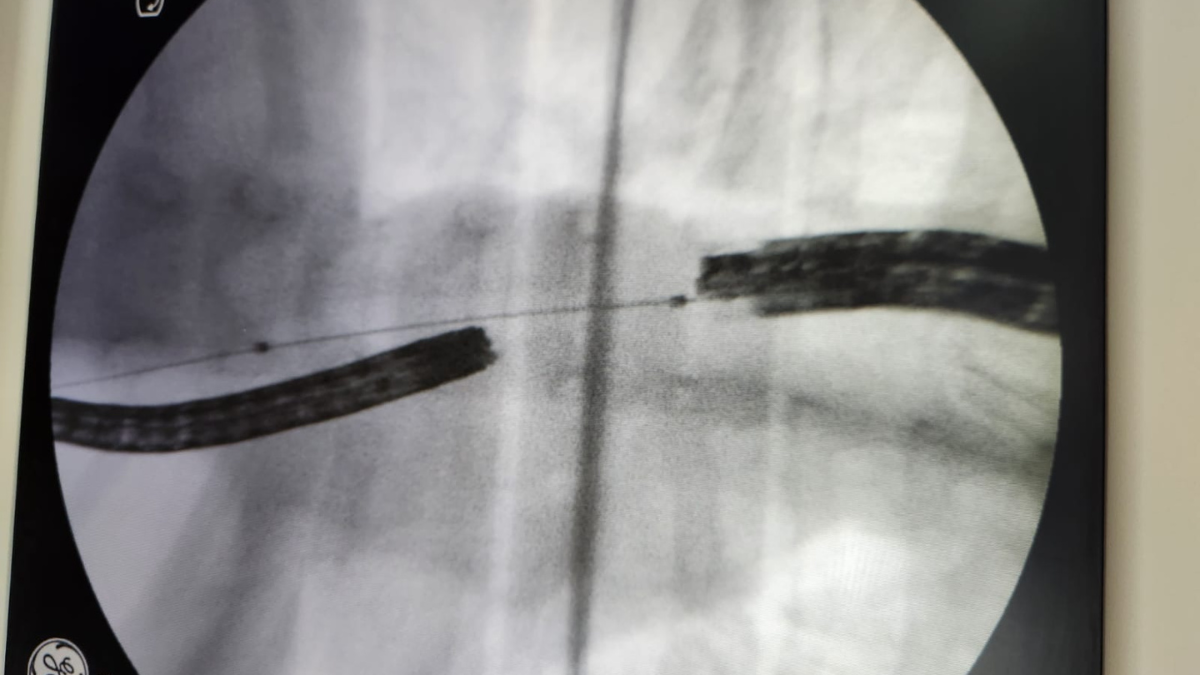

El especialista propuso la técnica rendezvous que significa encuentro o cita, en este caso de dos endoscopios. Lo que se hizo fue aprovechar el orificio del gastroestoma ubicado en el estómago e ingresar desde allí con un endoscopio y desde la boca con otro.

De este modo, una vez que pueden ver el sitio donde el esófago está totalmente cerrado, con una precisión milimétrica se puede perforar el esófago. Viendo con dos endoscopios a la vez resulta una cirugía de invasión absolutamente mínima.

Con control endoscópico y radiológico se avanzó con una guía, una vez que el procedimiento se realizó se progresó con un balón y se hizo una pequeña dilatación. Posteriormente, se dejó una sonda como tutor para que no se cerrara. Finalmente se efectuaron otras dilataciones que permitieron que el paciente pueda comer por la boca, comentó Isaguirre.